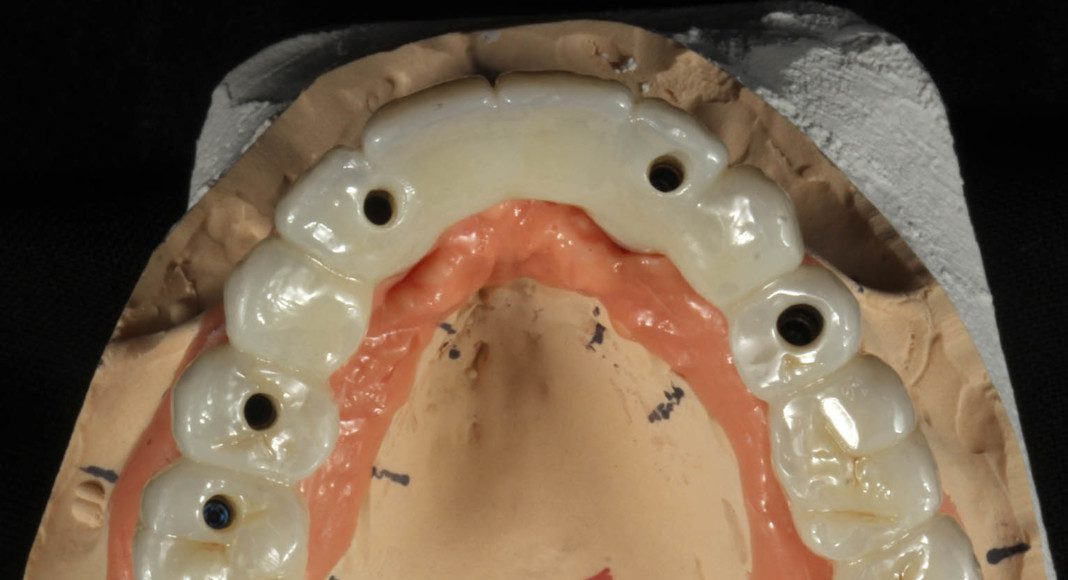

Occlusal view after 2 months. The final impression is made. This is the master cast of the implants and simulated gum tissue ready for the final zirconia bridge.

Occlusal view, day of delivery. If you look closely, you can see the final prosthetic screw (blue). This channel is covered with composite resin and patient comfort.